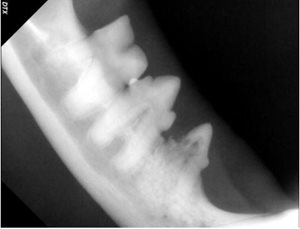

Another lovely feline friend, eight-year-old “Sir Ruby” had dentistry with us last month. During his annual health exam in May 2018, we observed that his teeth were moderately dirty, but by August 2018 there was significant suspicion of resorptive lesions noted by the veterinarian during a routine dental examination. The doctor noted the tell-tale red spot and significant gingivitis associated with his lower premolars. A dental procedure was recommended. During Sir Ruby’s dental surgery, gentle dental probing confirmed crown resorption and associated oral pain. X-rays of the affected teeth confirmed root resorption, as well. The teeth were extracted, Sir Ruby recovered quickly and is back to his normal happy self.

The speed in which this condition can progress, as shown in Sir Ruby’s case, is often surprising- and very much supports the importance of regular dental care and checkups. Please call Coxwell Animal Clinic and book your dental examination today!

Left Lower Premolars